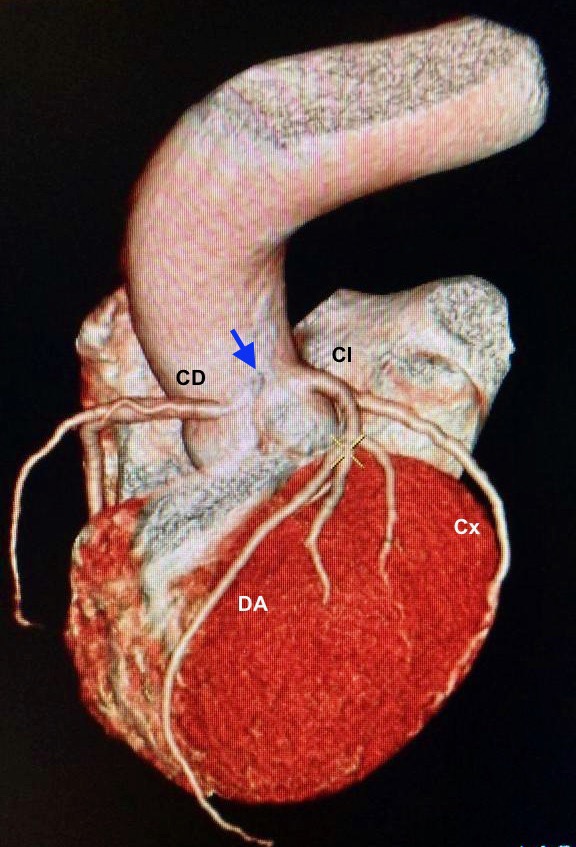

Presentamos el caso de un varón de 67 años de edad y múltiples factores de riesgo cardiovascular (dislipémico, diabético y exfumador), que acude a su cardiólogo del Hospital Vithas Pardo de Aravaca por dolor retroesternal al subir cuestas con sensación de taquicardia acompañante, que cedía con le reposo. La ergometría fue clínicamente positiva al presentar angina desde el minuto 2 de ejercicio. En el TAC de coronarias se objetivó el nacimiento anómalo superior de la coronaria derecha en el seno de Valsalva izquierdo, muy cerca a la unión con el seno derecho, existiendo un trayecto interarterial. Además, tanto la descendente anterior como la circunfleja presentaban placas no significativas del 30% y 40%, respectivamente.

El paciente fue intervenido quirúrgicamente realizándose un bypass coronario de arteria mamaria interna derecha (RIMA) a la coronaria derecha media. El postoperatorio transcurrió sin complicaciones y actualmente, 3 meses después de la cirugía, está asintomático y realiza vida normal.